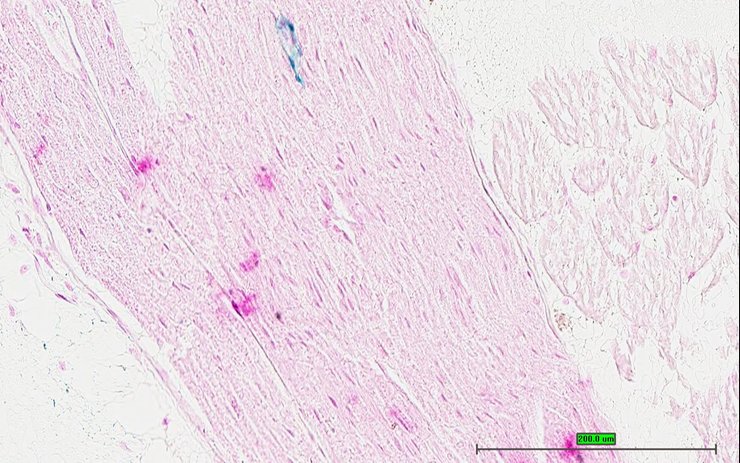

TS28: spinal cord Present UC Davis_1889546

Specimen UC Davis_1889547: postnatal adult; Cacnb2tm1.1(KOMP)Vlcg/Cacnb2+ (more )

Structure Level Pattern Image Note

TS28: spinal cord Present UC Davis_1889547